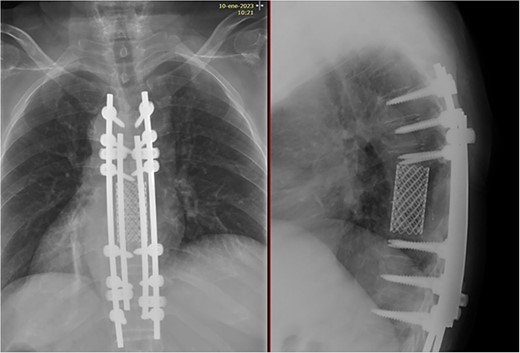

Posterior spinal instrumentation was performed with pedicle screws, three levels above and below T7. During the last pedicle coronal passing of the Tomita saw, a complete loss of abdominal and lower limbs potentials happened. Mean blood pressure above 85 mmHg was monitored, patient’s temperature was raised, and NASCIS protocol for acute spinal cord injury was initiated. After coronal cuts of the pedicles were completed, cephalic axial cut at T6 vertebral body and caudal cut at T8T9 intervertebral disk were performed. The piece was then removed en bloc (Fig. 4). Reconstruction with anterior mesh packed with allograft was performed. Posterior reconstruction was completed with double bar on each side for a more stable construct, with proximal tibia autograft covering the laminae for graft support and protection of the posterior spinal cord from muscular pressure (Fig. 5).

Total en bloc vertebrectomy of T7 and T8 and partial vertebrectomy of caudal T6.

Anterior reconstruction with mesh and posterior reconstruction with T4T5T6, T9T10T11 screws, and double bar.

Two years after surgery, adequate clinical recovery continues, with a high-degree satisfaction, persisting mild lumbar pain, and a slight weakness in the right foot. Pertinent X-rays show normal position of the implants with no implant loosening (Fig. 10).

X-rays showing normal position of the implants with no signs of loosening.